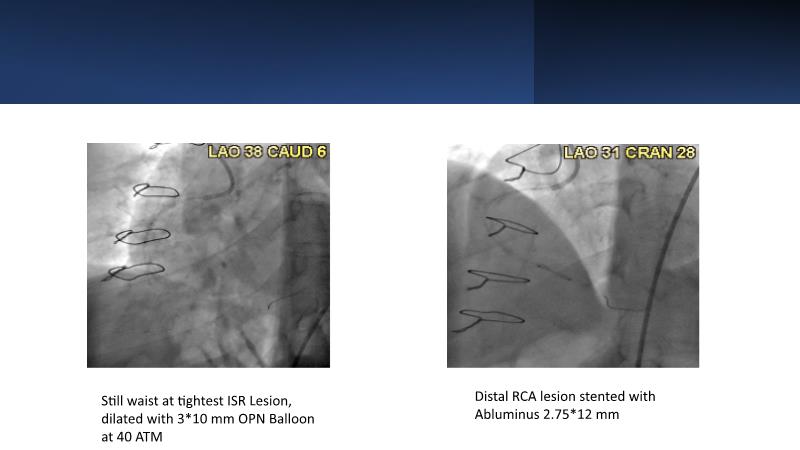

• To know why and how a fusion coating of DES+DCB stent platform is effective for the treatment of cardiovascular disease in diabetes mellitus patients via case presentations

• To understand why you can count on customised drug delivery platform of DES+DCB in complex settings with imaging-based evidence through case presentations